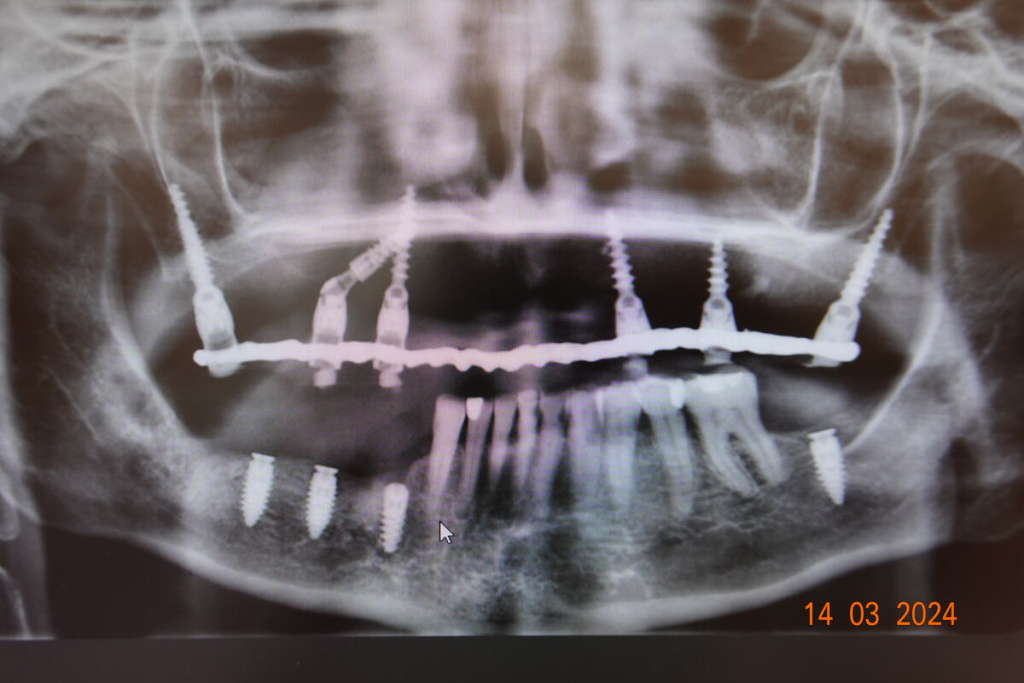

Technika All-on-X — I. fáze

Technika All-on-X — II. fáze

- 4–6 implantátů metodou All-on-X

Po 4–6 měsících nasazujeme trvalý můstek.

Používáme multivrstvý zirkon pro maximální estetiku, pevnost a dlouhou životnost.